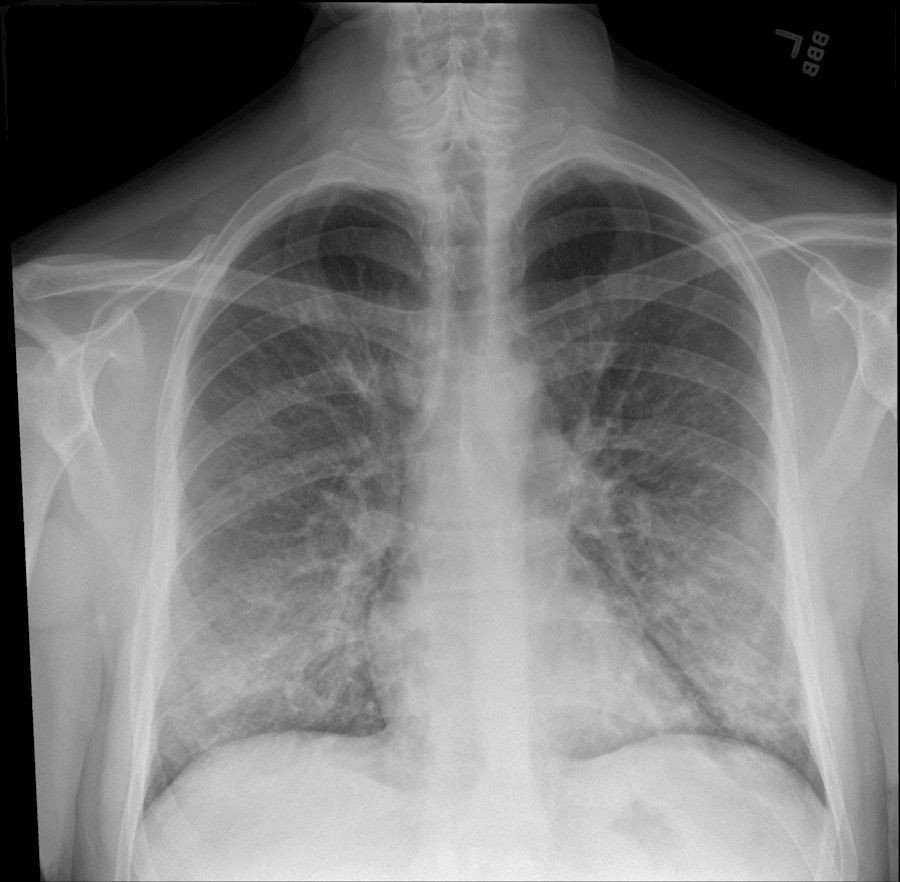

Las radiografías de tórax realizadas en adultos jóvenes y de mediana edad con covid-19 cuando llegan a urgencias pueden ayudar a los médicos a predecir quién tiene un mayor riesgo de enfermedad grave e intubación, informan los investigadores del Mount Sinai en el primer estudio de este tipo, que publica la revista `Radiology`.

La investigación identifica qué pacientes pueden necesitar ser hospitalizados e intubados en función de la gravedad de los patrones de coronavirus en los pulmones observados en las radiografías, utilizando un sistema de puntuación único para evaluar la gravedad Los resultados podrían ayudar a los médicos a identificar, clasificar y tratar a estos pacientes de alto riesgo más rápidamente.

Los investigadores se centraron en la radiografía de tórax de cada paciente para examinar los patrones de coronavirus en sus pulmones, observando las opacidades (marcas circulares blancas asociadas con COVID) y dónde estaban esos patrones.

Dividieron los rayos X en seis zonas (superior derecha, superior izquierda, media derecha, media izquierda, inferior derecha e inferior izquierda) y desarrollaron un sistema de puntuación de cero a seis para cuantificar la gravedad. La puntuación total dependía de cuántas zonas aparecían enfermedades. La puntuación de gravedad más baja variaba de cero a dos, y la más alta, de tres a seis.

De los 338 pacientes, 145 fueron ingresados. Los pacientes con puntuaciones más altas de radiografías de tórax tenían 6,2 veces más probabilidades de requerir hospitalización y 4,7 veces más probabilidades de ser intubardos.